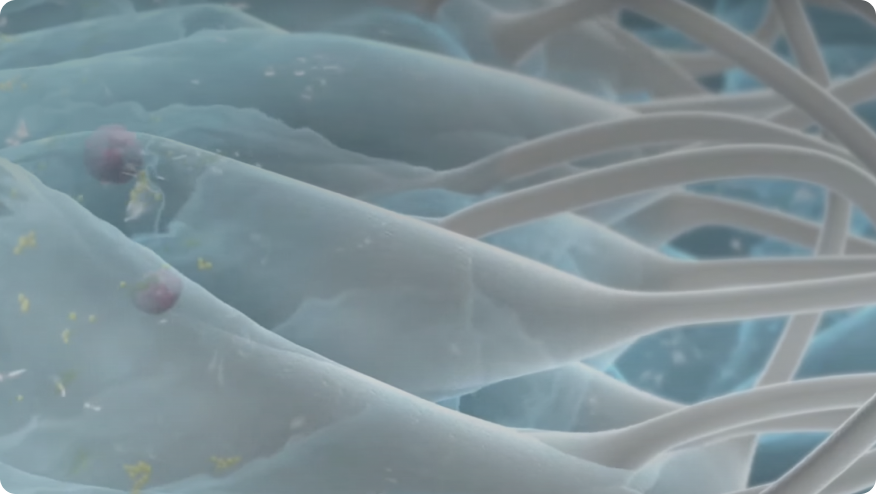

- Hydrofiber®-teknologi är ett mjukt, absorberande material som förvandlas till en gel vid kontakt med sårvätska

- Gelningsverkan skapar en optimal miljö för sårläkning*1,6,10,11,12

Låser in sårvätska och fångar bakterier*1-3

Kan bidra till att minimera sårinfektion och korsinfektion vid borttagning6,7